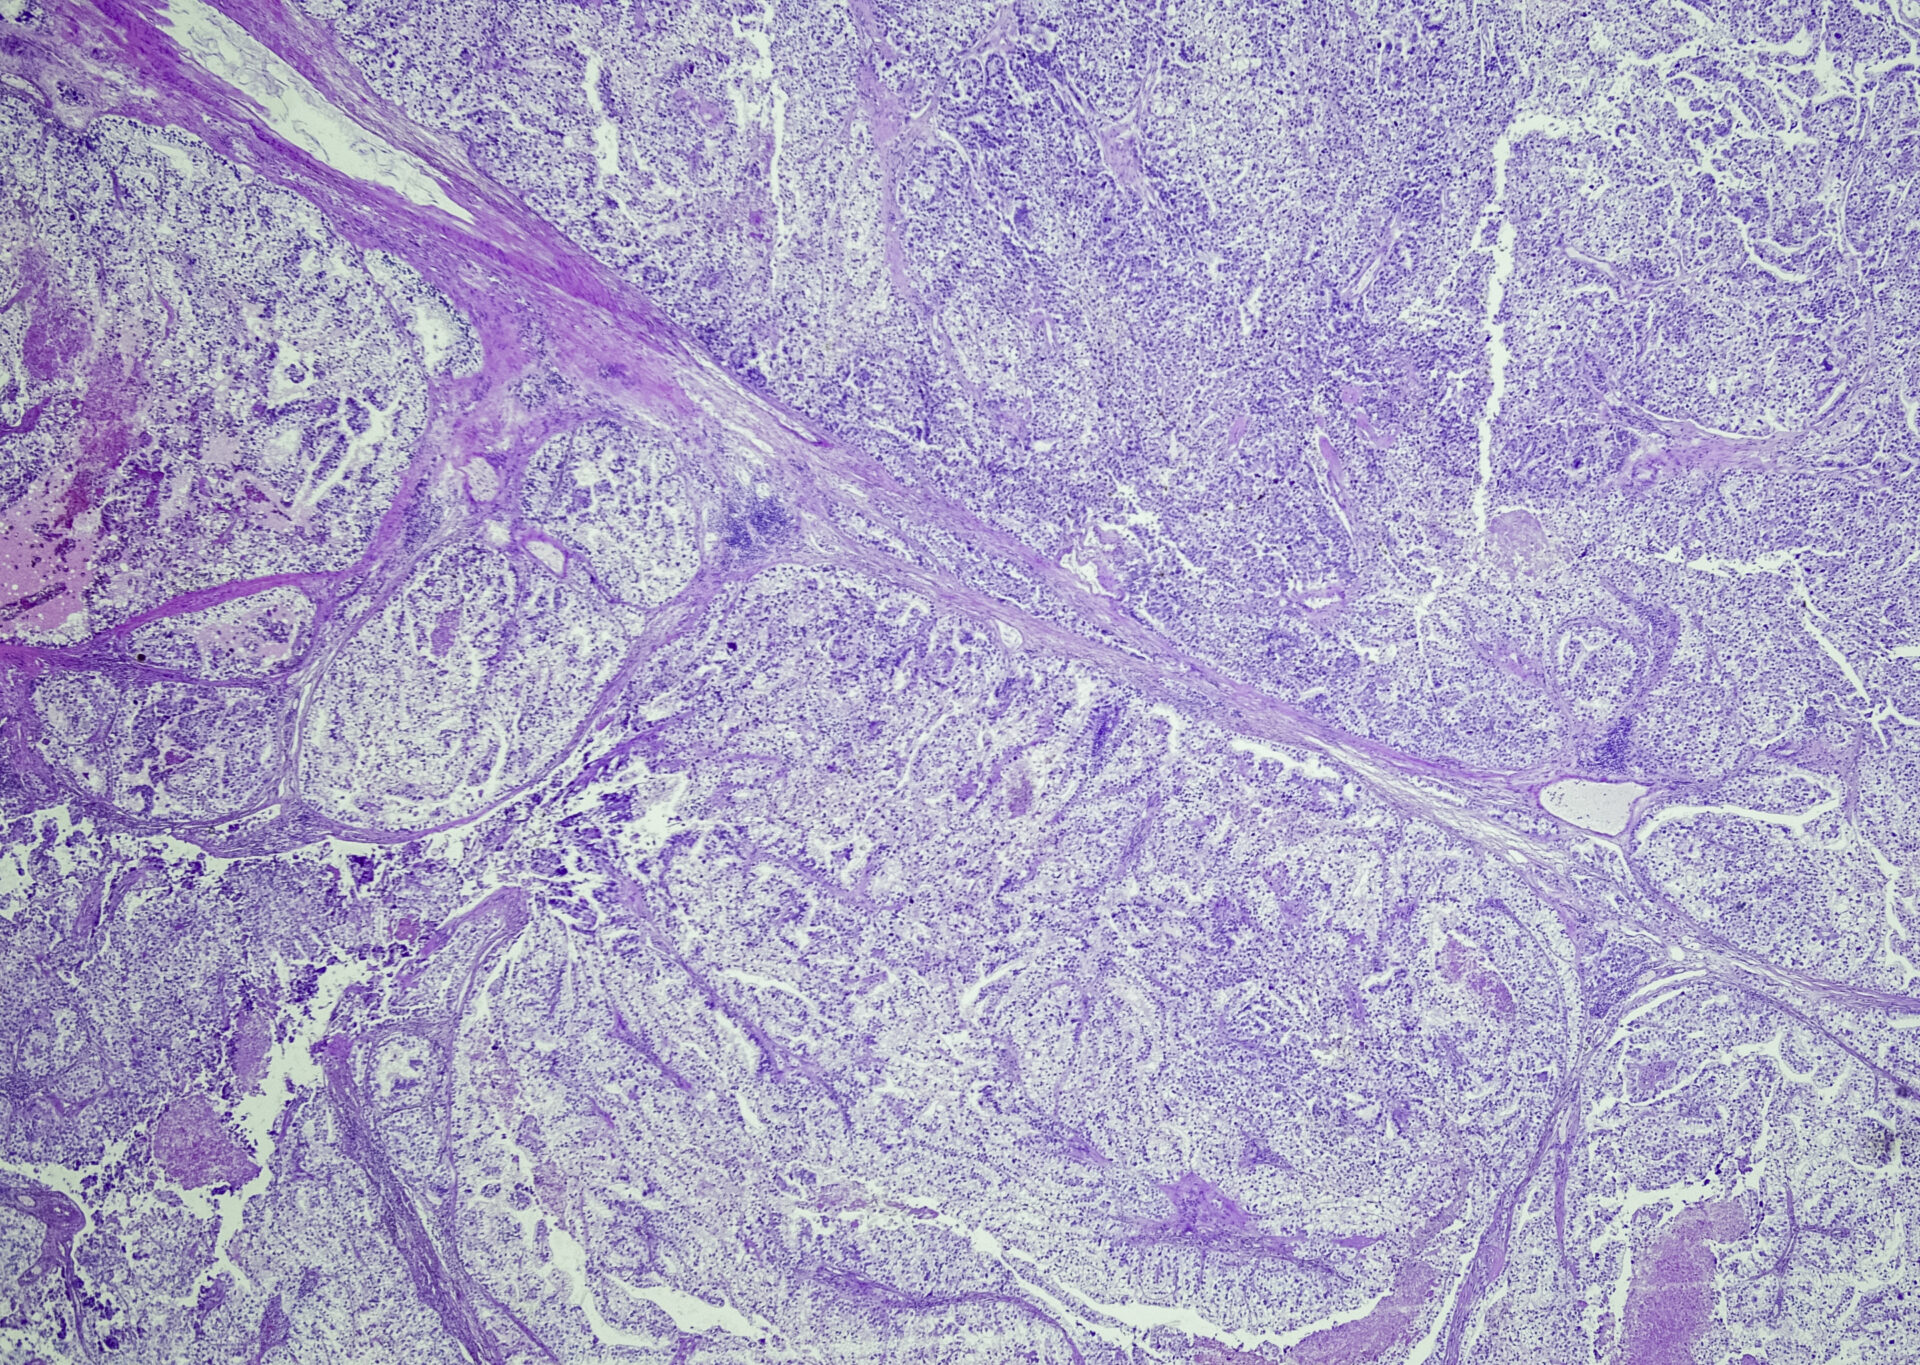

Das Nierenzellkarzinom gehört zu den tendenziell eher seltenen malignen Tumoren im Erwachsenenalter. In Bezug auf die medikamentösen Behandlungsoptionen hat diese Tumorentität in den letzten Jahren dennoch einen so rasanten Wandel vollzogen wie kaum eine andere maligne Erkrankung. Inzwischen steht nicht nur die zielgerichtete Therapie im Fokus beim fortgeschrittenen Nierenzellkarzinom, sondern auch Kombinationsbehandlungen.